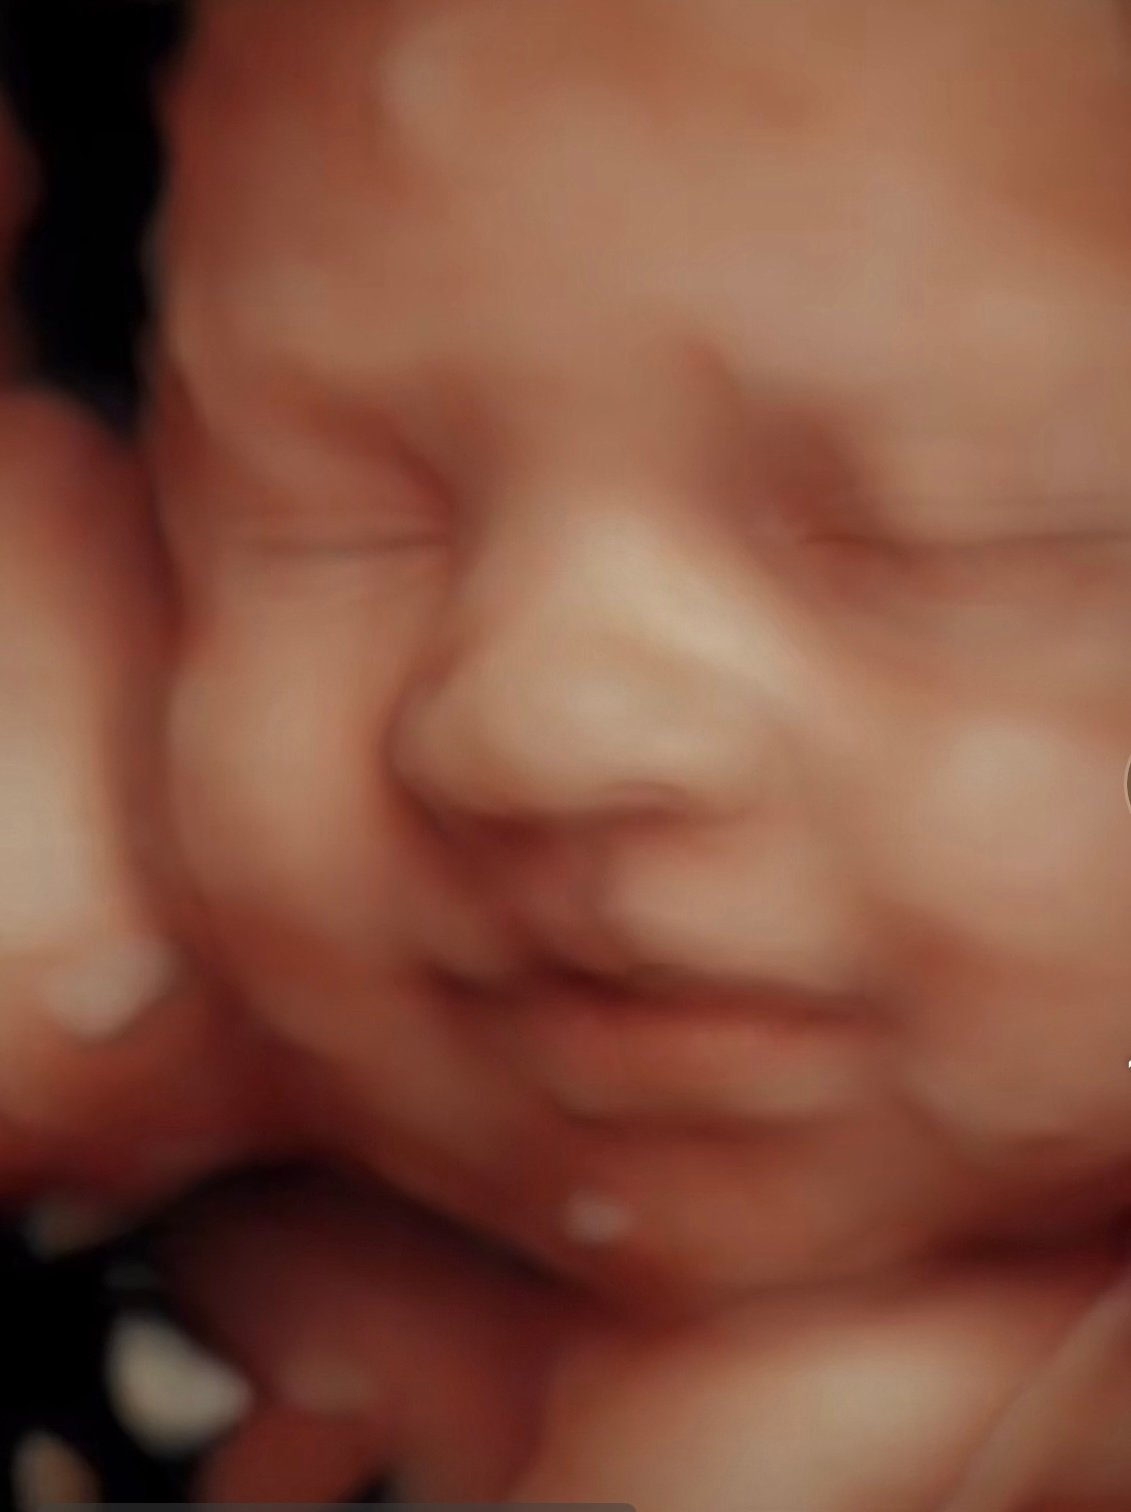

See your baby in 2D, 3D, and 4D. Experience the joy of meeting your baby before birth. Our elective ultrasounds are designed to create unforgettable moments for families. Enjoy our cozy environment of peace in an ultrasound in Tampa or Central Florida.

Our elective 4D sessions capture your baby’s real movements and transform them into breathtaking 8K baby portraits, memories you can keep forever.